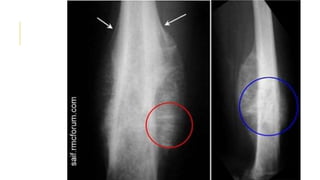

OSTEOSARCOMA

In its classic form, osteosarcoma is a highly malignant tumour

arising within the bone and spreading rapidly outwards to the

periosteum and surrounding soft tissues.

Osteosarcoma occurs predominantly in children and adolescents.

It may affect any bone but most commonly the long-bone

metaphyses, especially around the knee and at the proximal end of

the humerus.

On x-ray

 Some tumours are entirely osteolytic, others show alternating

areas of lysis and increased bone density.

The tumour margins are poorly defined. Often the cortex is

breached and the tumour extends into the adjacent tissues.

Streaks of new bone appear, radiating outwards from the

cortex – the so-called ‘sunburst’ effect.

Where the tumour emerges from the cortex, reactive new bone

forms in the angle between periosteum and cortex (Codman’s

triangle).